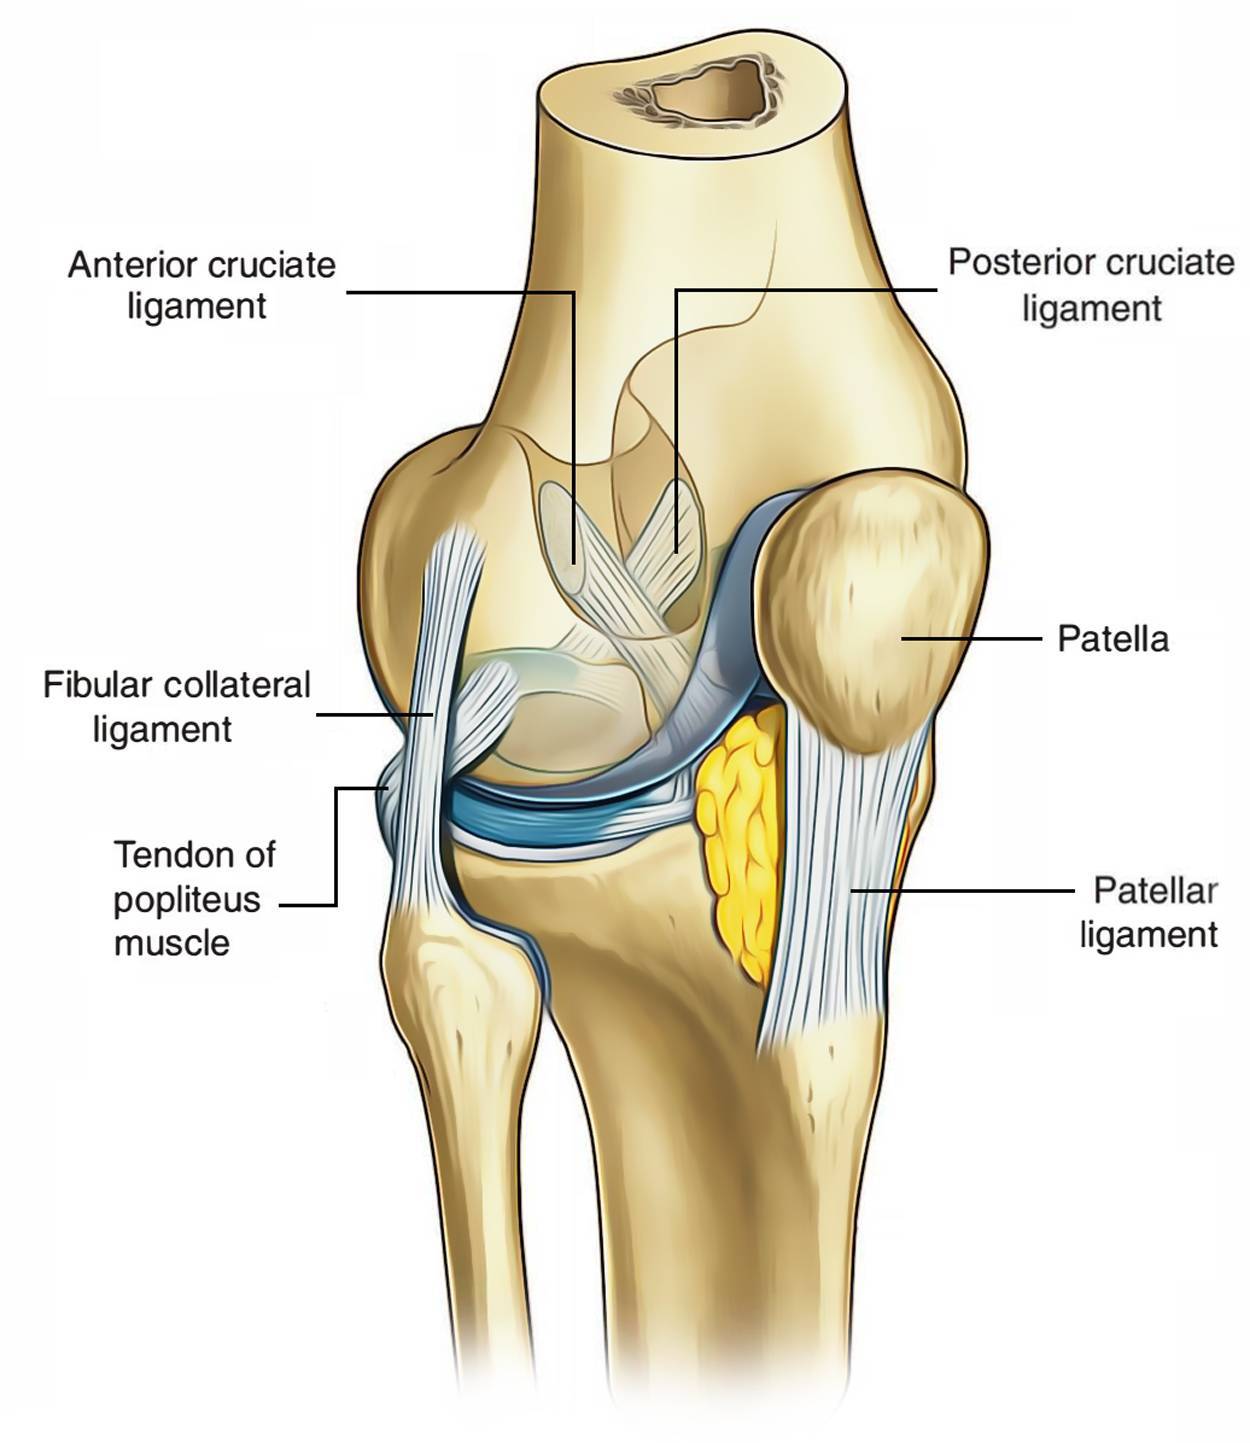

Анатомические изображения менисков и коленного сустава

Раздел: Иллюстрированные советы